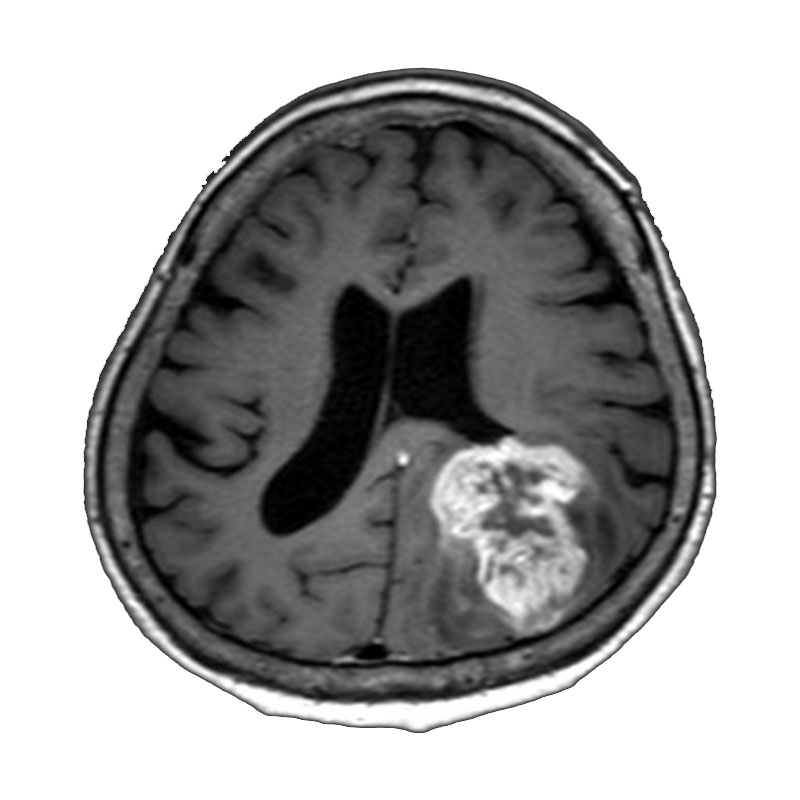

右側頭葉脳腫瘍

摘出術

南田/野本/佐伯